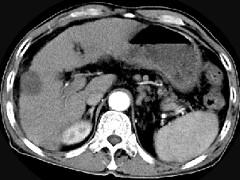

问题 男,63岁,肝区疼痛不适一个月,皮肤巩膜无黄染,AFP高于正常,CT所见如图,最可能的诊断是 ( )

选项 A.肝血管瘤 B.肝转移瘤 C.阿米巴肝脓肿 D.不典型肝癌 E.胆管细胞癌

答案 D